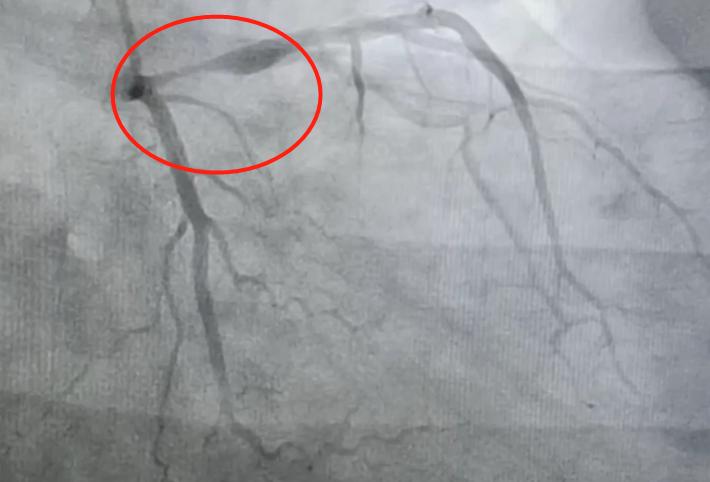

造影检查可以看出,前降支的开口和近端有一个95%的狭窄,局部伴有血栓存在。回旋支和右冠状动脉虽然有一些斑块,但是没见到明显的狭窄的地方,血流也正常,引起心梗的主要位置就是前降支的近端。